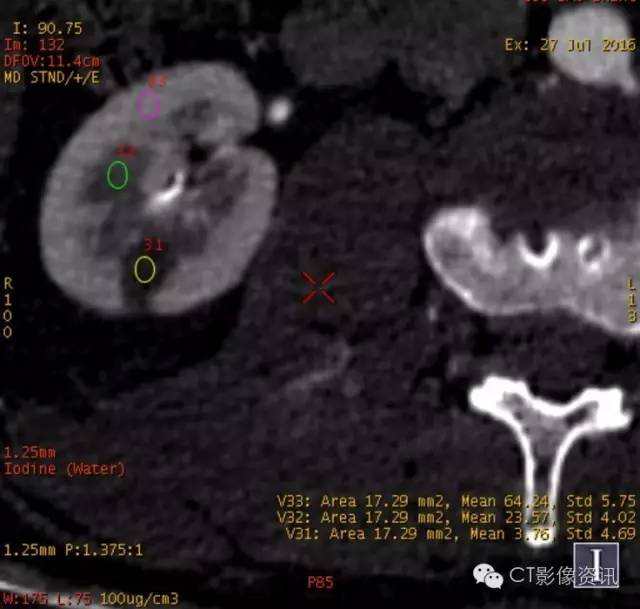

能谱曲线分析

左肾病变与左肾髓质具有较一致的同源性关系;右肾病灶呈“勺”状曲线,且与左肾病灶及肾皮质、髓质存在明显差异。

左肾病灶与左肾实质存在差异;右肾病变依然呈“勺”状曲线。

此病例为年轻男性,体检时发现双肾病变。进行CT平扫及GSI增强扫描,从病变位置、形状、增强特点可考虑左右肾为不同病变。进行能谱数据进一步分析发现,左肾病变基物质碘含量及能谱曲线与左肾髓质相似(皮质期明显),右肾病变基物质碘含量及能谱曲线与肾实质及左肾病变存在较大差异,并且右肾病变在三期增强扫描能谱曲线均为“勺”状,提示其中含有脂肪成分。综合以上参数考虑,左肾病变与左肾髓质关系密切,右肾病变含脂肪成分,趋向于错构瘤。基本排除左右肾病变为同一病变。